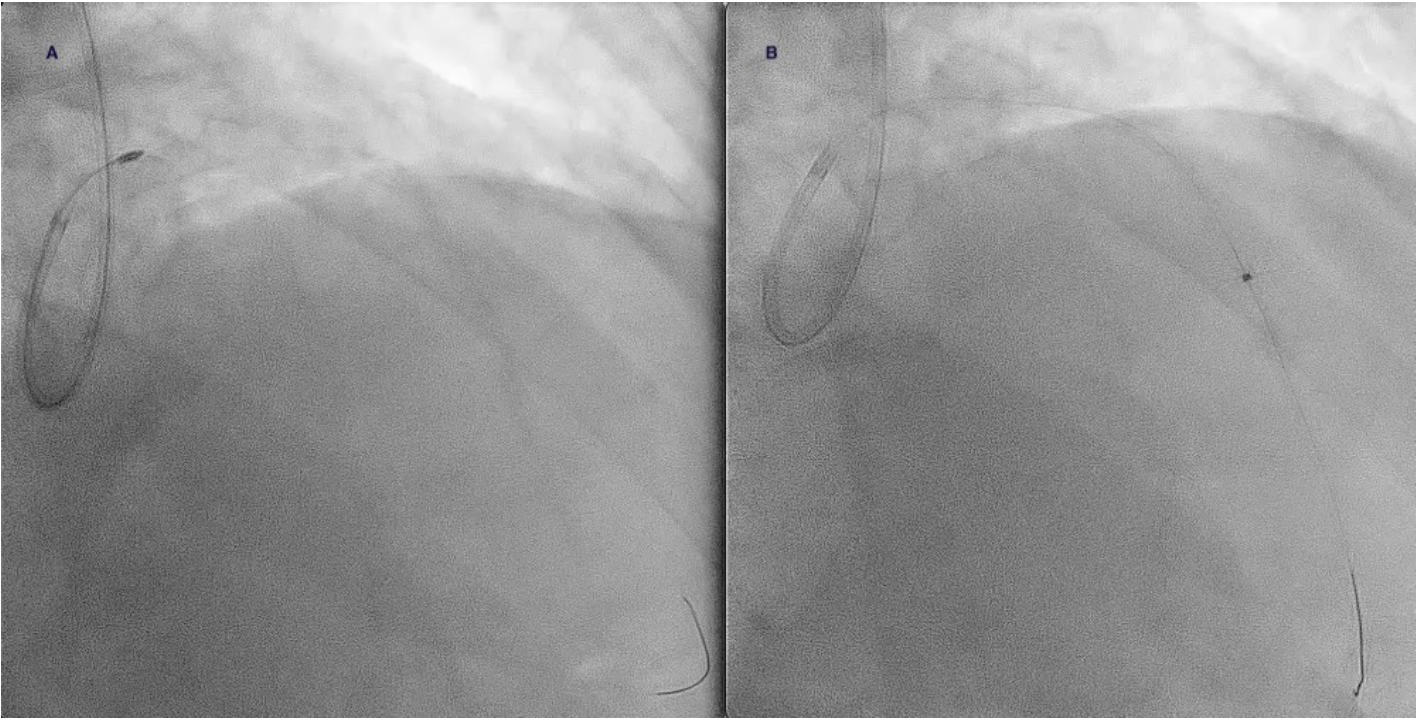

A 73-year-old man was hospitalized with acute coronary syndrome. Angiography showed severely calcified disease in the anterior descending artery and severe stenosis in the proximal, medial, and distal segments (Figure 1). Angioplasty was performed with an NC Trek Neo balloon (Abbott) with proper preparation of the plaque in the proximal and medial segments. Optical coherence tomography showed calcified plaque with a 360° ring and 1.2-mm thickness in the distal segment (Figure 2). Expansion attempts using a super high-pressure 2.5 x 10-mm OPN NC percutaneous transluminal coronary angioplasty (PTCA) balloon (SIS Medical) failed to fracture the calcification; rotational atherectomy with a Rotablator (Boston Scientific) was also unsuccessful. A 1.4-mm excimer laser coronary atherectomy catheter (Spectranetics) was also used (Figure 3) without fracturing the calcification, even after attempts with a super high-pressure balloon at 45 to 50 atm and being inflated for 40 to 60 seconds (Figure 4). Finally, a 3 x 28-mm Angiolite sirolimus-eluting stent (iVascular) was deployed in the proximal segments, followed by a 2.5 x 35-mm paclitaxel-eluting balloon (Medtronic) in the medial segment.